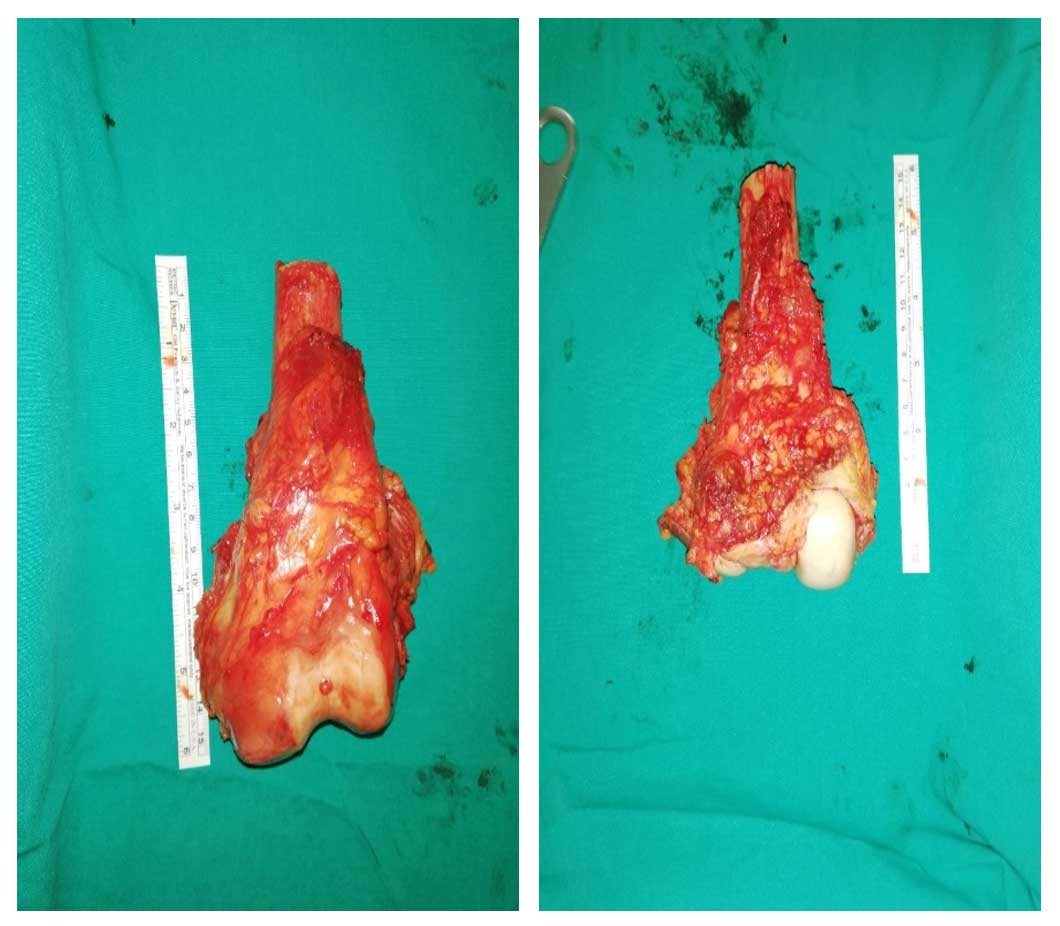

Ameliyat Esnası: Rezeksiyon materyalinin klinik görüntüsü.